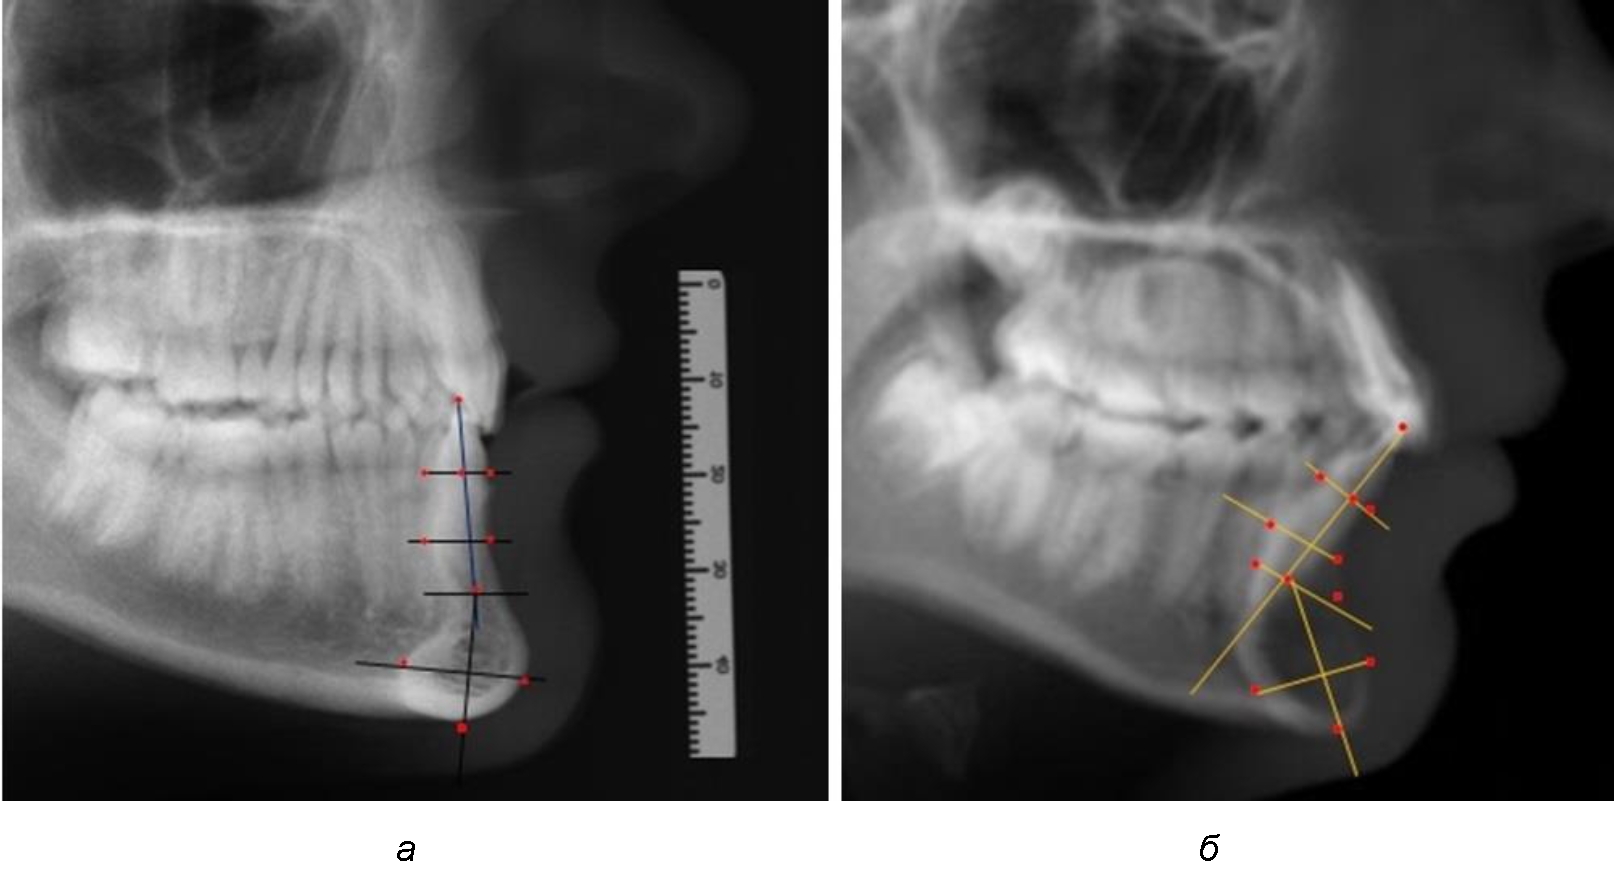

При анализе боковых телерентгенограмм использовали фрагменты гнатической части, на которых оценивали вертикальные и сагиттальные параметры резцового нижнечелюстного сегмента, на который наносили те же ориентиры, что и при анализе нативных препаратов и их рентгенограмм.

При необходимости и/или возможности проведения КЛКТ-исследования проводили анализ с сопоставлением фрагмента, что повышало точность диагностических мероприятий (рис. 2).

Рис. 2. Фрагменты ТРГ с ориентирами для измерения параметров резцового сегмента (а) и с наложением фрагмента КЛКТ (б)

Линейные и относительные показатели, полученные при исследовании нативных препаратов, могут быть использованы в ходе сравнительного анализа с данными результатов ТРГ. Результаты исследования ТРГ людей с физиологической окклюзией показали, что встречаются различные варианты нижнечелюстного сегмента, которые определяются вертикальными и сагиттальными параметрами, представленными в табл. 2.

Варианты резцовых сегментов нижней челюсти различные как по ширине, так и по высоте, а также по расхождению положения апикальных точек по Downs и Schwarz представлены на рис. 4.

Рис. 4. Особенности нижнечелюстного резцового сегмента на ТРГ у людей при среднем (а), широком (б) и узком (в) вариантах